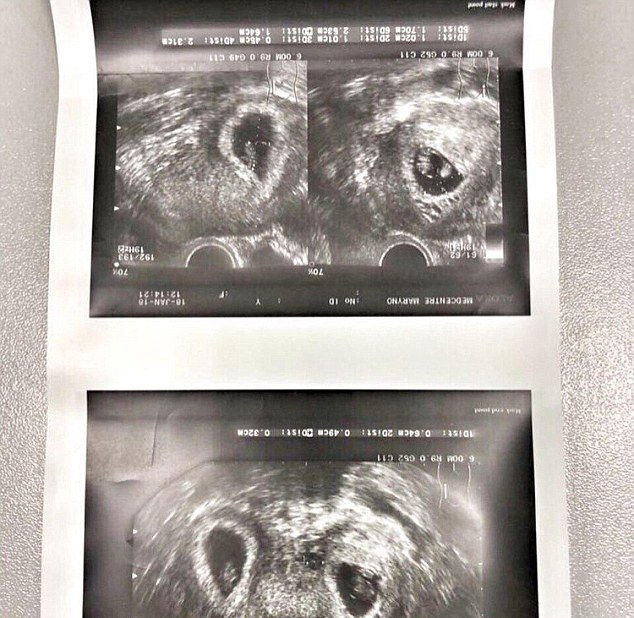

One woman out of a bunch of 1000 women is born with a uterus in shape of a heart (bicornuate).

This woman from Russia was born with the same disability. Doctors told her she will never be fortunate enough to conceive a child in her womb. But she proved all wrong and came out with flying colors.

The woman didn’t only conceive, but she conceived twins. All the doctors were shocked after they saw the case.

As this condition is considered to be a disability, it becomes really hard to give birth to a child and only a dozen cases with a condition like this have happened in the history.

Due to some complication and differently shaped uterus, the woman from Russia had to go under a Caesarean section birth method to bring those two little lives out of her and into this beautiful world.

She was blessed with a baby boy who weighed 7lbs and a baby girl who weighed a little less than 6lbs. Both the kids were born healthy despite the womb. The baby boy was named Evgeny and the girl was named Varvara.